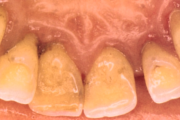

Krooniline parodontiit

Krooniline parodontiit on mikroobide poolt põhjustatud hammaste tugikudede põletik, mille tulemusena tekib progresseeruv alveolaarluu (nähtav röntgenograamil) ja periodontaalligamendi destruktsioon, igemetaskute moodustumine, igeme retsessioon või mõlemad kahjustused kombineeritult. Loe edasi »

Sümptomid:

- igemed veritsevad (19)

- igemed punetavad (21)

- ige on paistes (mädapunn)

- igemed on tursunud/vohavad (17)